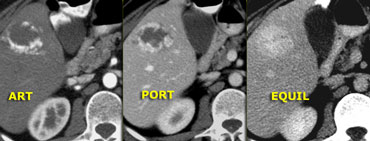

Typical hemangioma on dynamic MR Typical hemangioma on dynamic MR

Hemangiomas on dynamic MR will show the same enhancement characteristics as on contrast-enhanced CT.

The advantage of MR over CT is its higher sensitivity to contrast as will be shown in the next case.

Aspecific hypovascular lesion on CT Aspecific hypovascular lesion on CT

On the left an atypical, apparently hypovascular lesion on CT, possibly metastasis.

MR depicts enhancement better than CT MR depicts enhancement better than CT

Same case on dynamic MR.

Notice how MR depicts the nodular, peripheral, slowly progressing enhancement (blue curved arrow) which CT failed to depict.